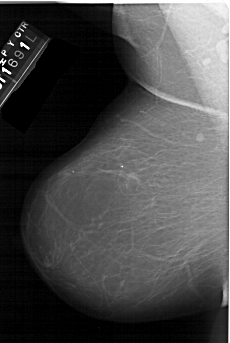

A_1542_1.RIGHT_MLO

RIGHT_MLO LINES 6166 PIXELS_PER_LINE 4141 BITS_PER_PIXEL 12 RESOLUTION 43.5 OVERLAY